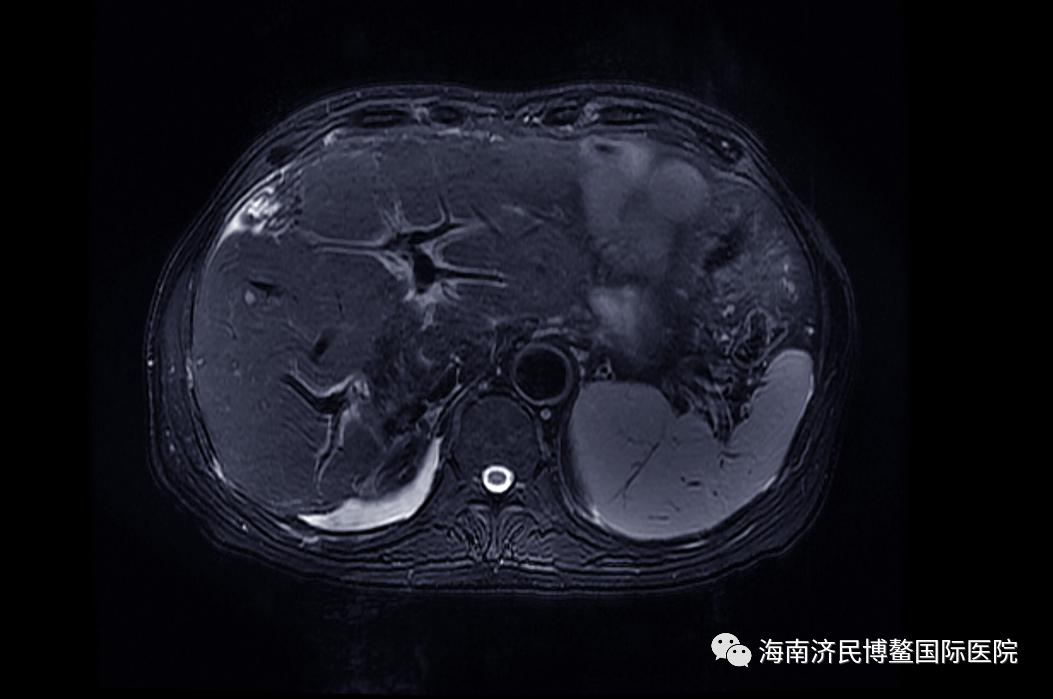

治疗前:5月8日最大肿瘤病灶体积77mm*95mm*100mm